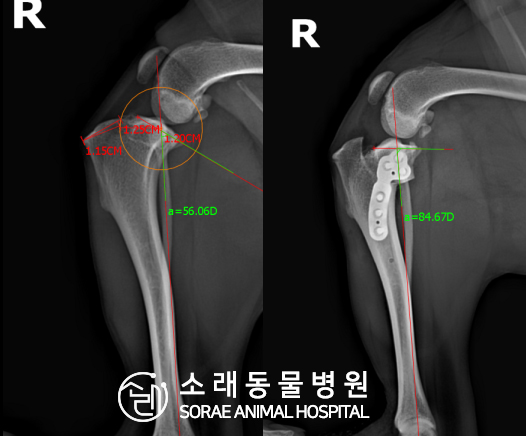

계산식으로 사전에 계획해두었던 플랜에 따라 경골을 절제하고

플레이트와 스크류를 사용하여 임플란트를 적용해 주었습니다.

반대 방향으로 밀려나 어긋나있던 대퇴골과 정강이가

제 자리를 찾으면서 무릎의 각도가 교정된 것을 확인할 수 있습니다